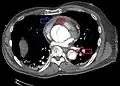

Computed tomography

Computed tomography angiography is a fast, noninvasive test that gives an accurate three-dimensional view of the aorta. These images are produced by taking rapid, thin-cut slices of the chest and abdomen, and combining them in the computer to create cross-sectional slices. To delineate the aorta to the accuracy necessary to make the proper diagnosis, an iodinated contrast material is injected into a peripheral vein. Contrast is injected and the scan performed using a bolus tracking method. This type of scan is timed to an injection to capture the contrast as it enters the aorta. The scan then follows the contrast as it flows through the vessel. It has a sensitivity of 96 to 100% and a specificity of 96 to 100%. Disadvantages include the need for iodinated contrast material and the inability to diagnose the site of the intimal tear.

CT with contrast demonstrating aneurysmal dilation and a dissection of the ascending aorta (type A Stanford)

Chest CT with descending (type B Stanford) aortic dissection (red circle)

Type A dissection with pericardial effusion as a result.